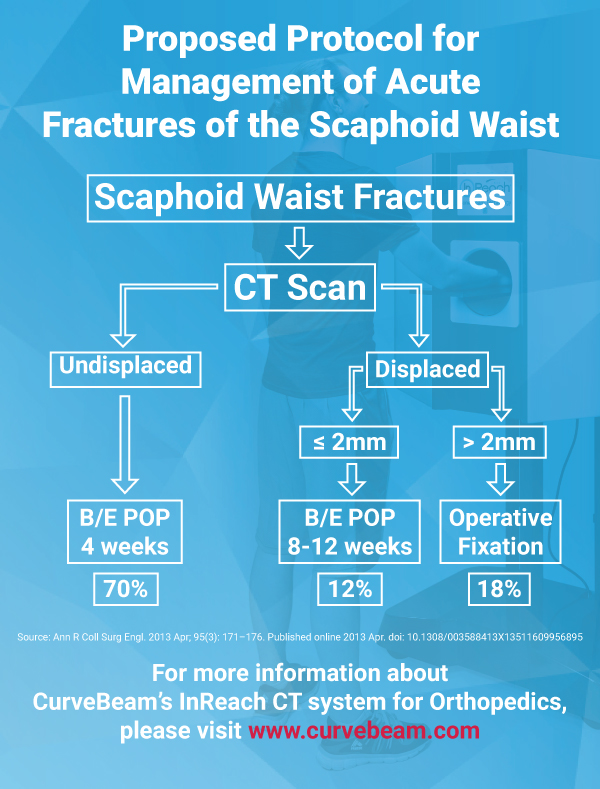

CT assessment of patients casted for a non-displaced scaphoid fracture shows union occurring at approximately 7.5 weeks, with a majority of fractures healing in less than 6 weeks, according to a 2016 study by Ruby Grewal et al. Similar studies using plain X-Ray demonstrated union time to be anywhere between 10 – 24 weeks. The authors noted the union time on CT may even be overestimated because the majority of patients’ first CT scan after casting was not until 6 weeks.

In a previous study, Professor Timothy Davis wrote CT studies demonstrate healing of a non-displaced fracture treated with a plaster cast can occur in as little as 4 weeks. If a fracture is displaced less than 2 mm, Davis said those CT studies suggest a plaster cast for 8 – 12 weeks.

CT is ideally performed for all scaphoid waist fractures in the first week after injury to classify whether they are displaced or non-displaced, said Professor Davis, an orthopedic surgeon at Woodthorpe Hospital in Nottingham, UK said in his research paper.

Fifteen percent of acute fractures of the scaphoid waist fail to unite if treated non-operatively in plaster, resulting in a persistent loss of function, according to the 2013 article. Plain X-Rays do not clearly show fracture features such as displacement and communition. Previous inter-observer studies have shown radiographs of scaphoid fractures are neither sensitive nor specific.